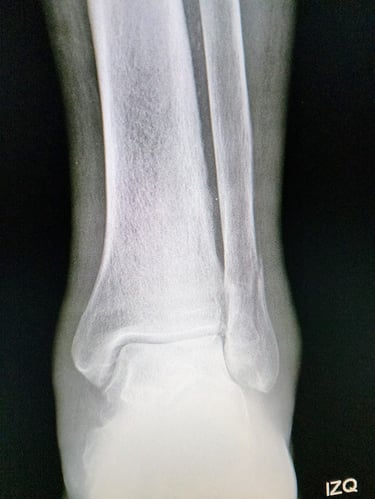

Radiografías: Permiten identificar el tipo y la ubicación exacta de la fractura.